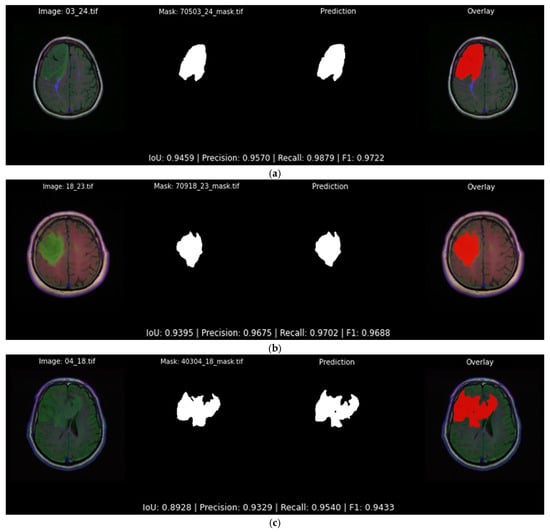

Figure 13 illustrates three typical highly accurate segmentations predicted by the best-performing softmax model presented in Table 5. All predictions follow the tumor boundaries closely, with IoU scores of 0.946, 0.940 and 0.892 for each example, respectively. In each case, the predicted mask aligns with the ground truth, not only predicting its general shape but also most of the details.

Figure 13.

Qualitative evaluation with examples in which the Attention U-Net and DiceBCE with softmax head predicts accurate tumor segmentation masks (IoU > 0.89). Each subfigure displays the original image, the ground truth segmentation mask, the predicted segmentation mask, and the original image overlaid with the predicted segmentation output mask (red) generated by the top-performing segmentation model: (a) showcases an example of a segmentation output of 0.945 IoU; (b) showcases an example of a segmentation output of 0.939 IoU; (c) showcases an example of a segmentation output of 0.892 IoU.